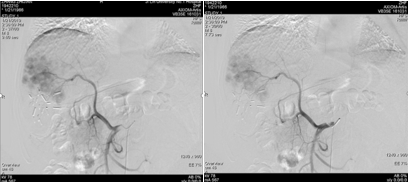

2018-12-11腹部CT检查提示,肝硬化、脾略大、门静脉高压;肝S6占位性病变,考虑原发性肝癌;肝S7段2枚结节;肝多发小囊肿,肝右叶钙化灶;双肾囊肿。

图片

图:腹部CT检查(2018-12-11)